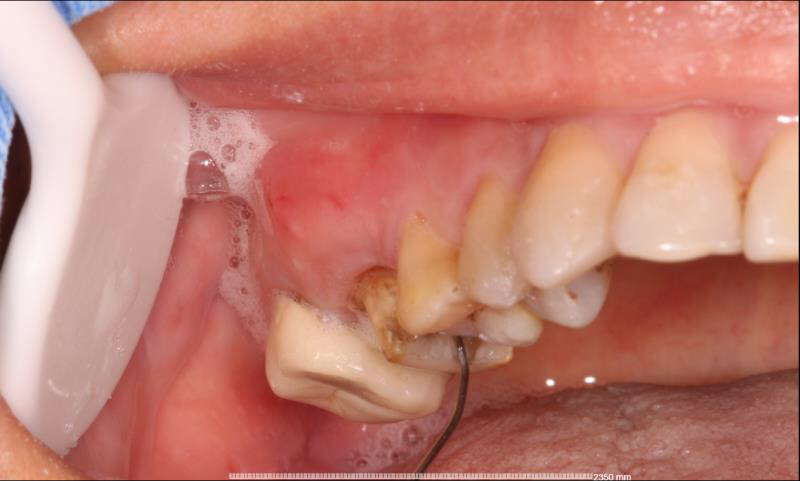

患者中年女性,右上6外院根管治疗多年,近期牙龈红肿,咀嚼疼痛,X线检查见根尖区大面积低密度影响,怀疑有遗漏的根管没有清理,用铒激光无损拆掉牙冠后进行根管再治疗,找到了遗漏的MB2,妥善的根管治疗完成后,重新戴上之前拆掉的牙冠,即解决了疼痛又为患者节省了一笔费用。